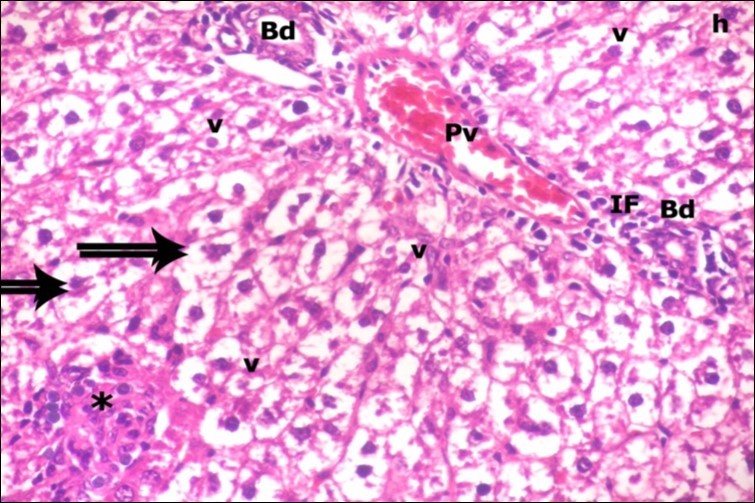

Examination of H&E stained sections of the 1st group (control group) revealed hepatic architecture of tightly packed cords of hepatocyte with vesicular nuclei and acidophilic cytoplasm radiating from the central vein (Figure 1). Portal area was composed of a portal vein, branch of hepatic artery and bile duct lined by single cuboidal cells with dark rounded nuclei. Blood sinusoids with their endothelial lining of Kuppfer cells were noticed in between hepatic cords (Figure 2). Examination of the liver sections of the 2nd group (vitamin E treated group) showed nearly the same histological features as the 1st group. The 3rd group (ZnONPs-treated group) showed a marked loss of the normal liver arrangement with dilated congested central veins and blood sinusoids. Most of hepatocytes had large cytoplasmic vacuoles and darkly stained nuclei other hepatocytes were ballooned (Figure 3). The portal area showed dilated congested portal vein with proliferation of bile duct, necrotic foci in between the hepatocytes with inflammatory cellular infiltration (Figure 4). The portal area showed also elongation of the endothelial lining of dilated congested portal vein and increasing amount of connective tissue fibers (Figure 5). There was congested hepatic artery with increasing thickness of its muscular layer (Figure 6). Bile duct showed proliferation with stratification of its epithelial lining (Figure 7).

Figure 4.A photomicrograph of a section in the liver of ZnONPs-treated adult albino rat showing dilated congested portal vein (Pv), proliferation of bile duct (Bd), inflammatory cell infiltration (IF) and ballooning of hepatocytes (double arrows) with darkly-stained nuclei (h) and vacuolated cytoplasm (v). Area of necrotic focus is also present (star). (H&E X400)

Foci of cellular infiltration were detected in the liver parenchyma. Such result is parallel with Sharma et al., 14 who stated that the liver revealed hepatocellular necrosis and accumulation of mixed inflammatory cells around the necrotic area. Edinger and Thompson 32 attributed the presence of necrotic foci to lysis of cells and formation of cell debris, which could initiate phagocytic infiltration. In the current study the portal area revealed portal vein dilatation and congestion. Hu et al. 33 explained that the congestion and dilatation of central and portal veins may be due to portal hypertension. Bile duct proliferation was evident in the current ZnONPs- treated group. This result is in agreement with Pati et al. 34 who documented that a ductular reaction is the proliferative response to many types of liver injuries. It is now generally accepted that the liver contains hepatic stem cells/ progenitor cells in which are considered as a subpopulation of liver cells termed oval cells. Under the condition of severe and chronic liver injury caused by drugs, toxins and viruses, these oval cells are induced to proliferate and differentiate both into biliary epithelial cells and into mature hepatocytes 35.